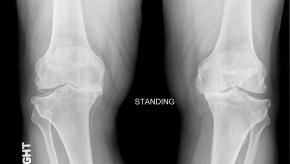

Read ArticleOsteoarthritis Update August 2015

Different Phenotypes for Osteoarthritis of the Foot. Osteoarthritis is often characterized as either a symmetric polyarticular (often involving DIPs, PIPs and CMC1), asymmetric oligoarticular or monarticular (knee or hip OA), but OA may also affect the foot.